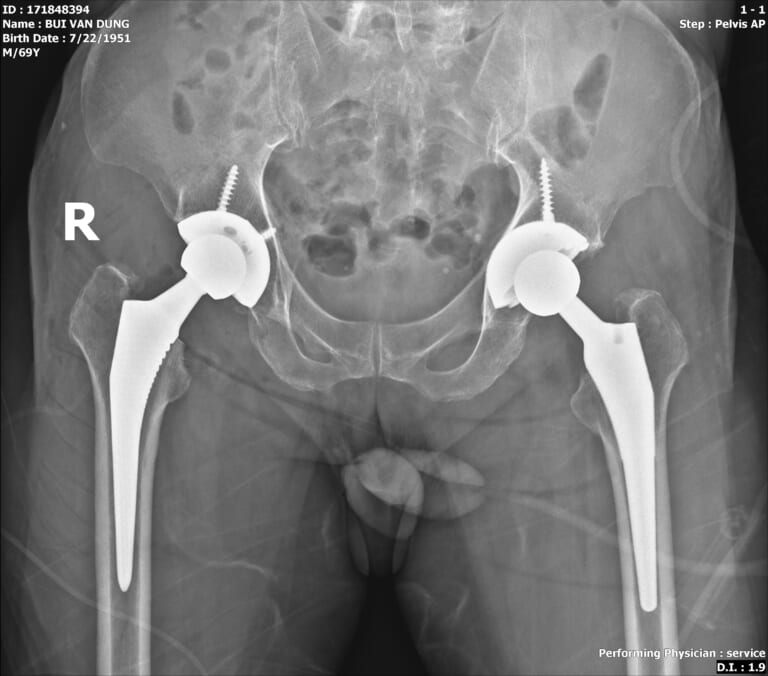

Hay một trường hợp thay khớp háng tại Hồng Ngọc là bệnh nhân Bùi Văn Dũng (70 tuổi, Đống Đa) bị hoại tử cả hai bên khớp háng khiến ông thường xuyên bị những cơn đau hành hạ cả ngày lẫn đêm.

Thạc sĩ. BSCKII Giang Lam cho biết: “Tình trạng thoái hóa khớp của bệnh nhân vừa do khớp bị lão hóa vừa do nghiện rượu nặng dẫn đến viêm khớp biến chứng hoại tử chỏm xương đùi trên và gây thoái hóa khớp. Bệnh nhân bị thoái hóa cả hai bên nhưng khớp háng trái tiến triển nhanh và nặng hơn với nhiều triệu chứng điển hình”.

Với mức độ nghiêm trọng này thì thay khớp háng được coi là “cứu cánh” cuối cùng để bệnh nhân sớm có thể quay trở lại cuộc sống bình thường.

Ca phẫu thuật thành công và bệnh nhân đã có sự hồi phục nhanh chóng nhờ kiên trì thực hiện các bài tập phục hồi chức năng tại viện. Người nhà bệnh nhân Dũng chia sẻ: “Sau khi mổ xong bổ tôi hồi phục rất nhanh, chắc chỉ một tuần thôi là chân đã hết đau và sau một tháng đã đi lại bình thường”.

width= Khớp háng nhân tạo của bệnh nhân sau khi được thay